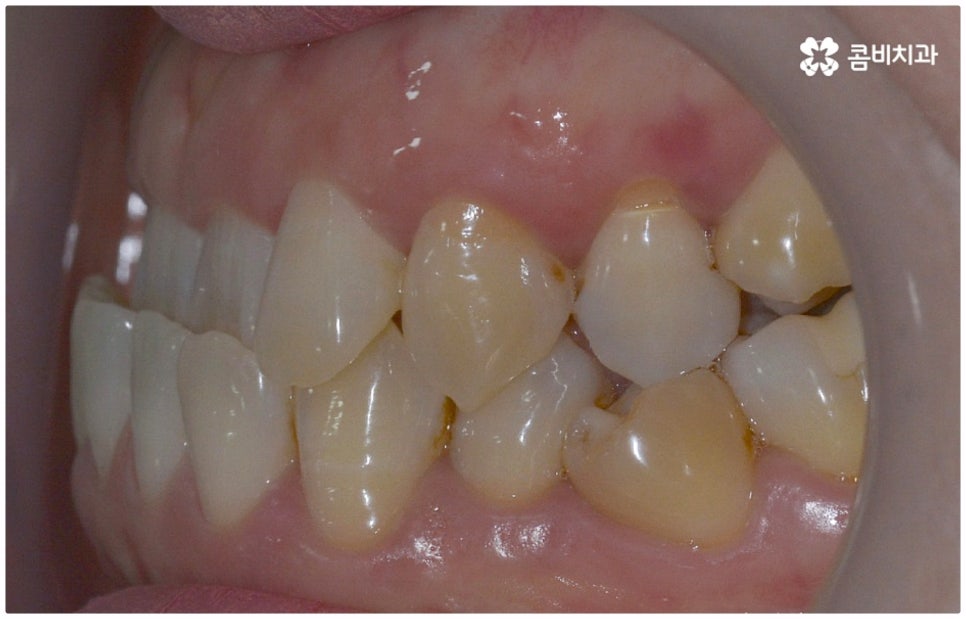

출처 아카이브 열기위아래 치열이 제대로 맞물리지 않으면 음식물을 씹을 때 어려움을 느끼거나 발음상 문제가 생길 수 있습니다. 이것을 부정교합이라고 하며, 그 종류는 상악과 하악의 골격적인 전후방 관계를 기준으로 1급, 2급, 3급으로 나눌 수 있어요. 위아래 어금니는 잘 맞물리는데 치열이 조금씩 삐뚤어져 있거나 치아 사이가 벌어져 있는 등 살짝씩 어긋난 부정교합은 1급, 위 어금니가 더 앞으로 나가있는 부정교합은 2급 (ex. 돌출입), 그리고 아래 어금니가 더 앞으로 나가있는 부정교합은 3급 (ex. 주걱턱) 으로 분류하게 되는데 이 중 오늘 살펴보려고 하는 것은 부정교합 3급에 해당하는 반대교합에 대한 거예요.

정상적인 교합은 윗 앞니가 아래 앞니를 살짝 덮는 정도로 윗니가 조금 더 앞으로 나와 있으면서 위아래 치아가 어금니까지 잘 맞물리는 것을 말하는데 반대교합은 위아래 앞니가 거꾸로 물리는 증상을 보이기 때문에 저작 활동 및 발음 조성이 원활하지 않게 되며 반대교합교정 등 적절한 치료를 받지 않고 방치할 경우 점점 더 주걱턱이 강화되는 쪽으로 뼈가 성장할 수 있어 될 수 있는 대로 빠른 시일 내에 원인을 분명하게 알아보고 그에 맞는 치료를 받는 것이 중요하다고 할 수 있어요.

골격적인 원인이 아니라면 위턱과 아래턱의 위치나 크기에는 이상이 없는데 치아의 맹출 각도 및 방향의 문제로 인해 치아가 반대로 맞물리게 된 치성 반대교합에 해당하는 경우라고 할 수 있는데요. 그 원인으로는 선천적인 치열의 문제 (아래턱 앞니 치축이 앞으로 기울거나 위턱 앞니 치축이 뒤로 들어감), 유치가 너무 빨리 빠지고 영구치가 자리를 제대로 잡지 못해 생긴 문제, 후천적인 습관 (혀를 내밀거나 손톱을 깨무는 등 치열에 좋지 않은 영향을 주는 행위를 지속적으로 반복) 으로 인한 문제 등등을 살펴볼 수 있으며, 보통 이런 경우 앞니 4~6개 치아 일부에 국한된 문제이기 때문에 보다 빠르고 간단하게 교정 치료가 가능하므로 꼭 성장기에 치료를 시작하지 않고 성인이 된 후라고 해도 비교적 쉽게 개선이 될 수 있습니다.